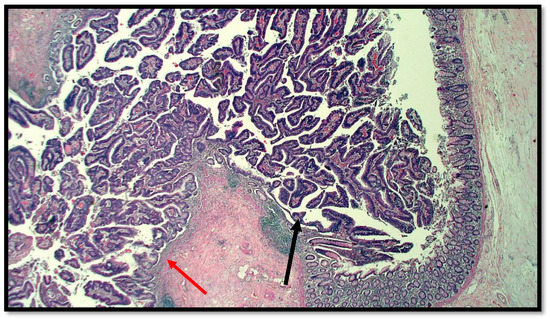

Figure 2.

Photomicrograph showing goblet cell carcinoid of the appendix. Cytological detail of the “ring with bezel” cells (hematoxylin–eosin, original magnification: 20×). An example of a ring with bezel cells is indicated with a red arrow.